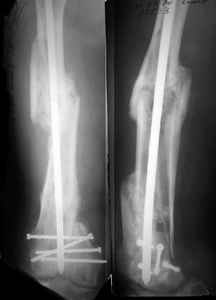

Attached are few examples from our Hospital:

A. Difficult reductions, even in retrograde nailing (my preference, easier control of "small" distal fragment) and it is much, much harder to do it anterograde (Alex, do you have one good case in your collection of anterograde nailing in very distal fractures - as you have suggested that I

should have done it in my previously posted case?

Malpositioning is much too common (recurvatum, varus - valgus).

B. Fixation loosening: distal cutting of the nail, non-unions do happen (cases attached).

Locking Plating has more distal screws than any nail, fixed angles and provides much better fixation, especially in osteoporotic bone.

A new toy is more interesting and fashionable. And anyway it is not panacea, i have already seen presentations with LISS failures like the attached one presented by D.Seligson. And people also demonstrated incisions say that the method is not so LESS invasive as it supposed to be.